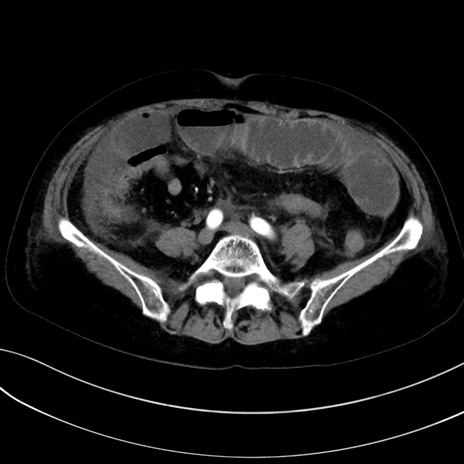

症例13 CT(横断像)1日半後